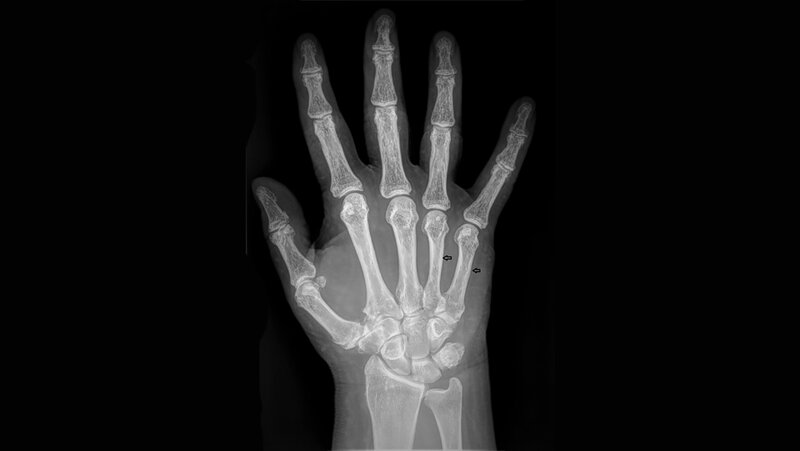

Anomalien und Normvarianten: Skelettale Veränderungen 3.29: Brachydaktylie und Brachymetacarpie

Die Brachydaktylie ist Teil einer Gruppe der Gliedmaßen-Malformationen mit Knochendysostosen. Die isoliert auftretende Brachydaktylie ist selten. Sie kann mit anderen Fehlbildungen der Hand einhergehen, wie zum Beispiel Syndaktylie oder Polydaktylie.

Schlüsselwörter: Brachydaktylie, Röntgen, CT, MRT